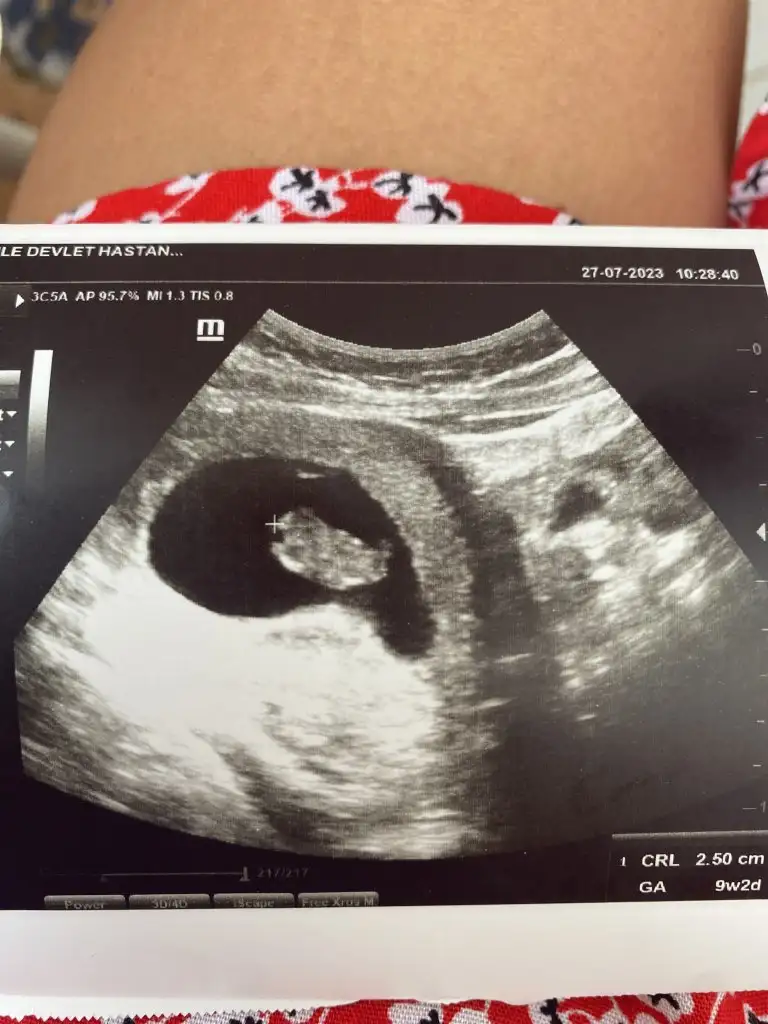

2 doktor farklı söyledi biri kız, biri erkek dedi nub neresi oluyor canım çok anlamıyorum doktorun birisi çıkıntı var ama çok küçük henüz dedi gösterdi diğeride yok boş dedi

Evet küçük bir çıkıntı var. Nub teorisi diye google de arama yaparsınız örneklerde görürsünüz. Bu kalp bölgede popo kısmının o tarafta oluyor. Eğer düz ilerleme olursa kız, hafiften yukarı ya da dik ise erkek. Fakat bebeğim duruşu da bunu etkileyebilir ama tan düz giden nub genelde kız çıkar.

Nub belli mi bizim